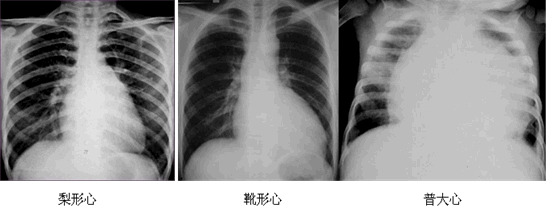

二尖瓣型梨形心左心房增大二尖瓣狭窄(最常见)

主动脉型靴形心左心室扩大法洛四联征、主动脉瓣膜疾病、高血压心脏病

普大型普大心心界向两侧扩大心肌病心脏病后期、心包积液等